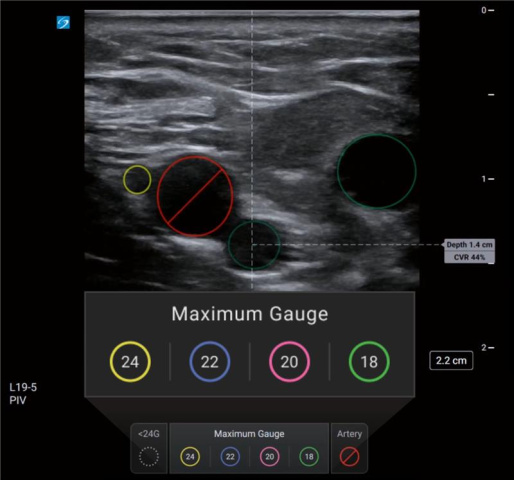

Did You Know that Sonosite has a New Vascular Access Education Partner?

Did You Know that FUJIFILM Sonosite has a new partner to provide vascular access education to our customers? With education being one of our core pillars, we strive to ensure that your department and clinicians are adequately equipped with the knowledge and training to administer care to patients using point-of-care ultrasound. …

Training MattersPoint-of-Care Ultrasound (POCUS) empowers clinicians with real-time diagnostic capabilities and procedural practices at the patient's bedside, which can improve the speed and accuracy of patient care. Hands-on POCUS training for clinicians at educational workshops is imperative in maximizing the benefits of using ultrasound systems effectively. …